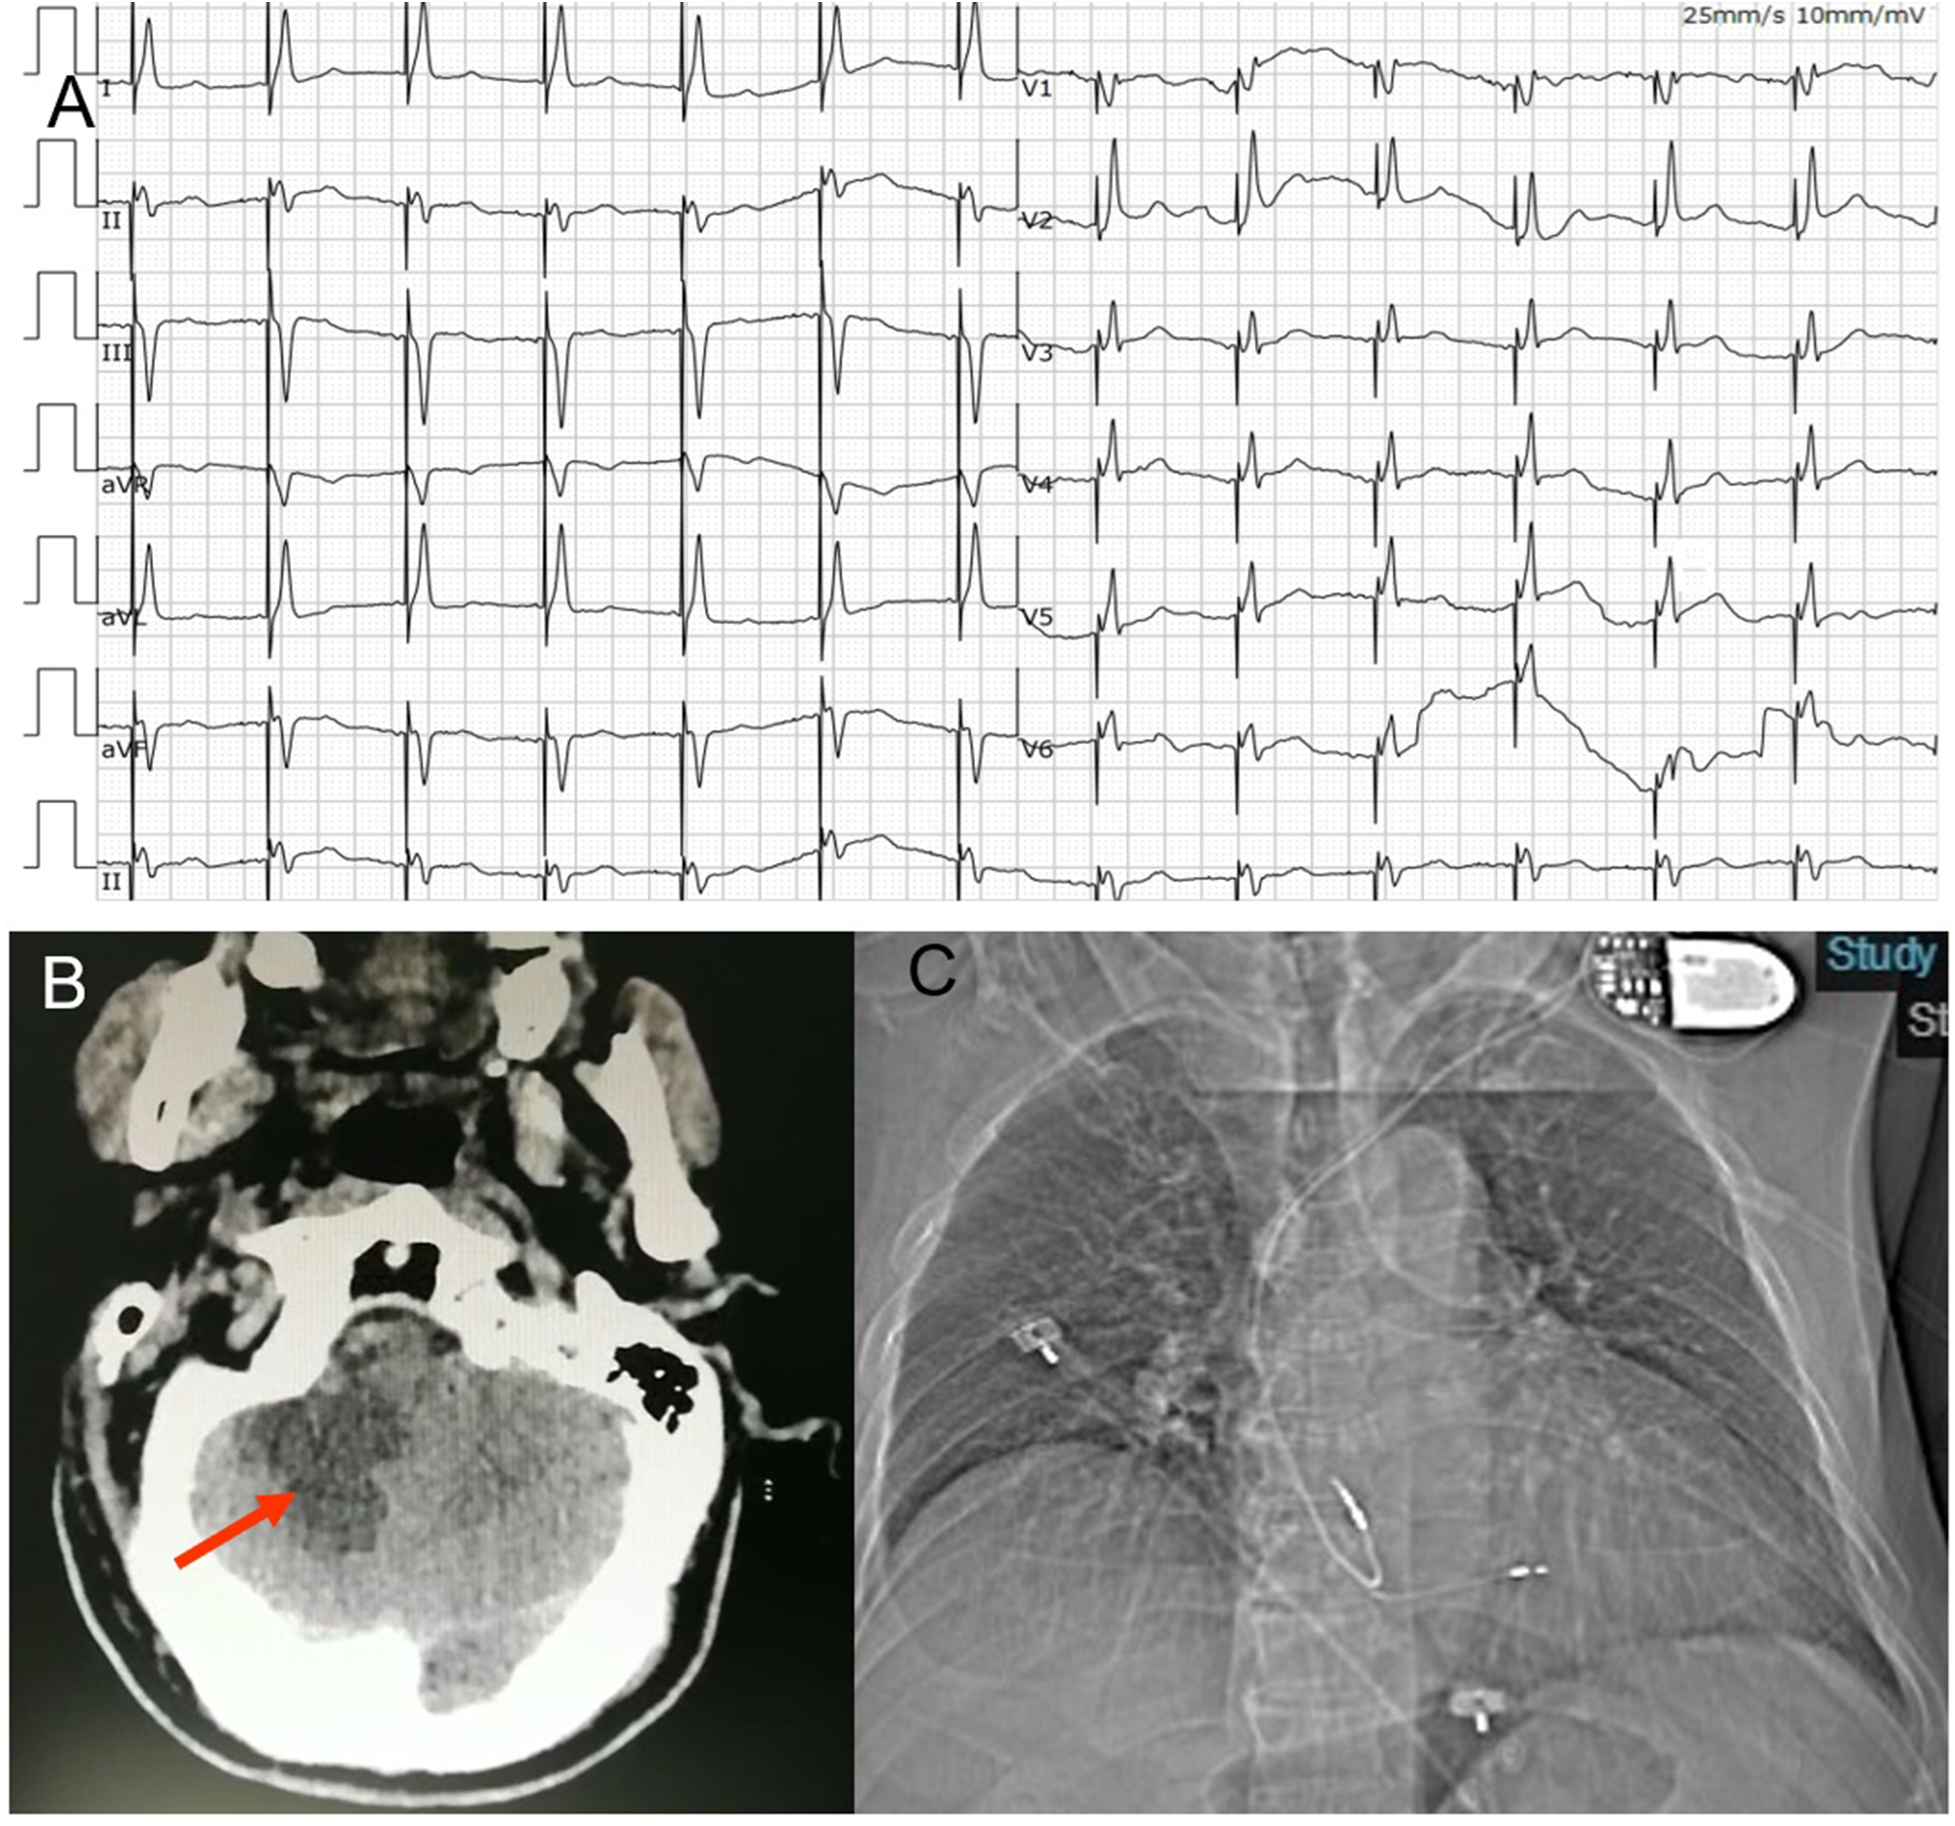

Figure 2

(A) ECG post permanent pacemaker implantation. The ECG suggested deep septal pacing with the tip of the lead close to the left posterior branch. (B) Craniocerebral CT- scan showed an infarction in his right cerebellum (arrow). (C) Anteroposterior chest radiograph of dual-chamber pacemaker implantation.

On the second day, at 16 h after the procedure, the patient suddenly became developed unclear symptoms after forced defecation, including vomiting, vague speech, cold sweat, consciousness reduction and involuntary movements. His vital signs showed an elevated blood pressures at 150/89 mmHg. The neurological examination presented no cranial nerve dysfunction, symmetric deep-tendon reflexes, a negative Babinski sign and a slight weakness in all muscles. Coordination and sensory functions could not be tested. Upon this, a craniocerebral CT-scan was performed, showing an infarction in his right cerebellum (Figure 2B). The patient was transferred to the neurology department for further treatment.